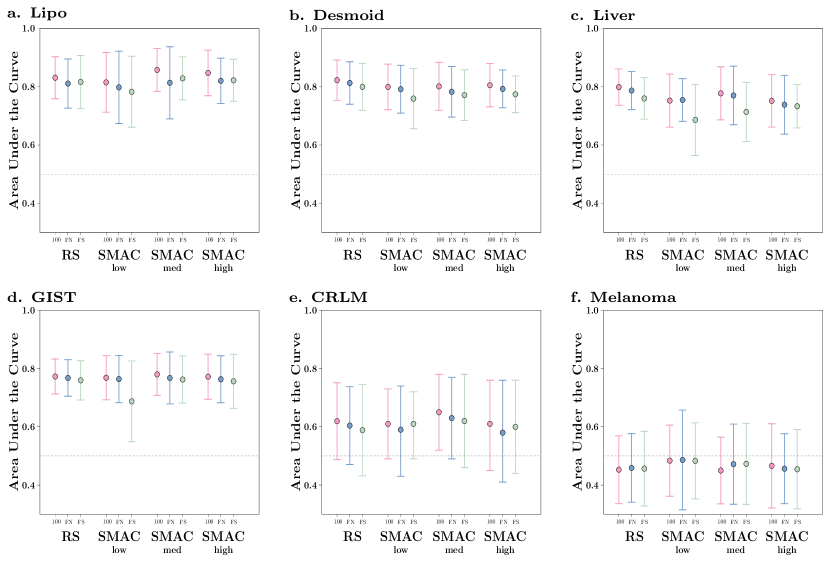

The performance on the test set of the WORC algorithm random search and Bayesian optimization through SMAC using various ensembling approaches in the six public datasets is depicted in Figure 4. Generally, the performance of SMAC was on all computational budgets similar to that of the random search, as the confidence intervals show substantial overlap. Similarly, the confidence intervals for the different ensemble methods show substantial overlap. However, on average, the top100 ensembling method consistently outperformed the FitNumber and ForwardSelection methods on all datasets, for all SMAC computational budgets, and for the random search.

The performance of the single best configuration on the validation set of the WORC algorithm and SMAC is reported in Table A.2. The random search consistently outperformed SMAC on the lowest computational budget (0.02 - 0.07 higher ), except for one dataset (Lipo). On the contrary, SMAC on the highest computational budget consistently outperformed the random search (0.02 - 0.08 higher ).

In the six publicly released datasets, we have compared the performance of the WORC framework to Bayesian optimization through SMAC and different ensembling approaches. While only by a slight margin, combining the best 100 workflows consistently outperformed the FitNumber and ForwardSelection ensembling approaches in all experiments on all datasets, Hence, besides requiring no fitting and thus less computation time than the other methods, combining the best 100 workflows also performs best. On all computational budgets, the performances on the test datasets of SMAC and the random search were similar. These results support our choice for random search in our optimization algorithm. For the validation sets, SMAC substantially outperformed the random search when using a high computational budget. This higher validation performance, which is what both SMAC and the random search try to optimize, did however not translate to a higher generalization performance, i.e., performance on the test set, indicating overfitting of SMAC on the validation dataset. The worst overfitting was found on the Melanoma dataset, in which the validation performance was 0.20 higher than the test performance. Although other optimization strategies might show an improvement over the random search during optimization on the validation dataset, these results clearly show the limits of optimization and the importance of generalization.